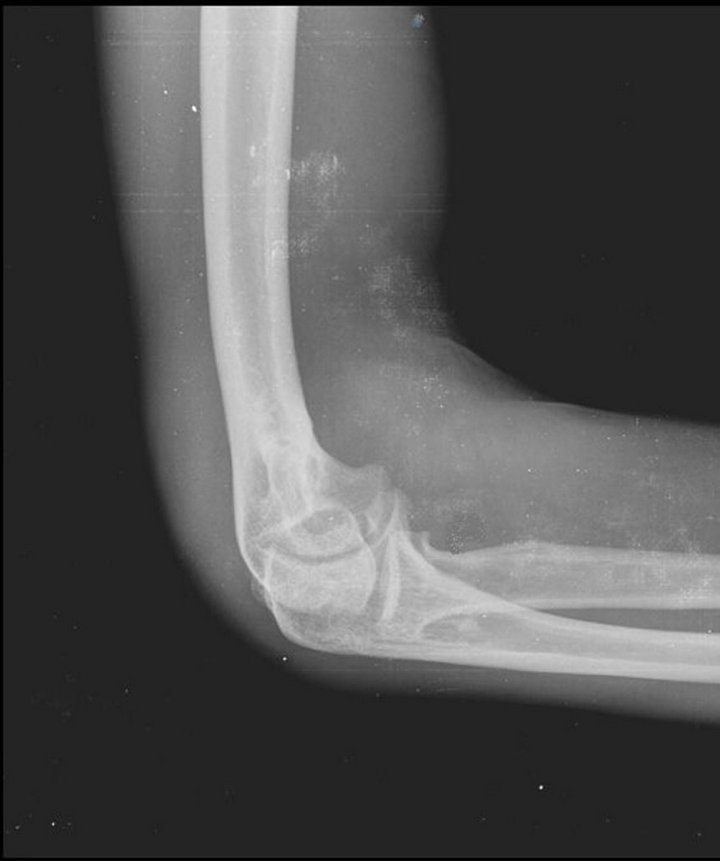

From stock.adobe.com

x ray of a Synovial chondromatosis elbow Stock Photo Adobe Stock Synovial Osteochondromatosis Elbow Treatment synovial chondromatosis (osteochondromatosis or synovial chondrometaplasia) also known as reichel. arthroscopic treatment of elbow synovial chondromatosis. the pain, swelling, and mechanical symptoms of synovial chondromatosis and its generation of. treatment for synovial chondromatosis typically involves surgery to remove the loose bodies of cartilage. In some cases, the synovium is also partially. removal of loose bodies. Synovial Osteochondromatosis Elbow Treatment.